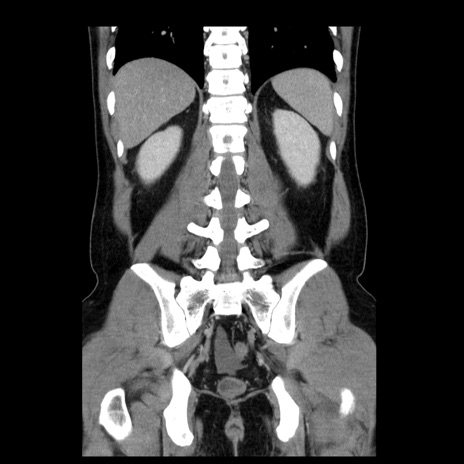

症例4(冠状断像)

【症例】30歳代男性

【主訴】腹痛、嘔吐

【現病歴】昨晩から突然の腹痛あり、その後嘔吐、軟便も出現。腹痛が改善しないため救急搬送となる。2日前にしめ鯖の食事歴あり。

【身体所見】意識清明、苦悶様、BP 135/90mmHg、BT 35.7℃、腹部:平坦、やや硬、心窩部〜臍部に自発痛、圧痛あり、筋性防御+、反跳痛-

【データ】WBC 8100、CRP 0.57